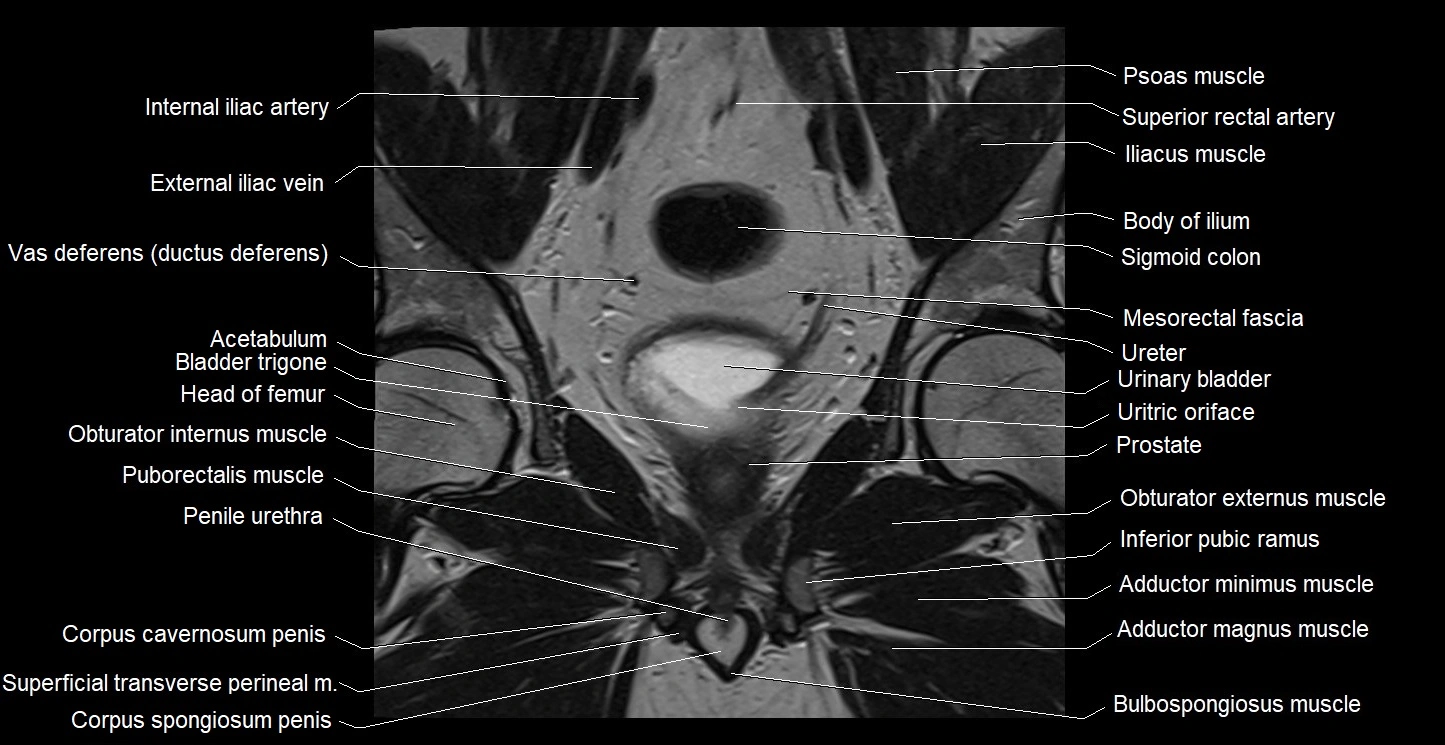

- Acetabulum

- Adductor magnus muscle

- Adductor minimus muscle

- Body of ilium

- Bulbospongiosus muscle (Male)

- Corpus spongiosum

- External iliac vein

- Head of femur

- Inferior pubic ramus

- Internal iliac artery

- Mesorectal fascia

- Obturator externus muscle

- Obturator internus muscle

- Penile urethra

- Peripheral zone of prostate

- Puborectalis muscle

- Sigmoid colon

- Superficial transverse perineal muscle

- Superior rectal artery

- Trigone of urinary bladder

- Ureteric Orifice

- Urinary bladder

- Vas deferens